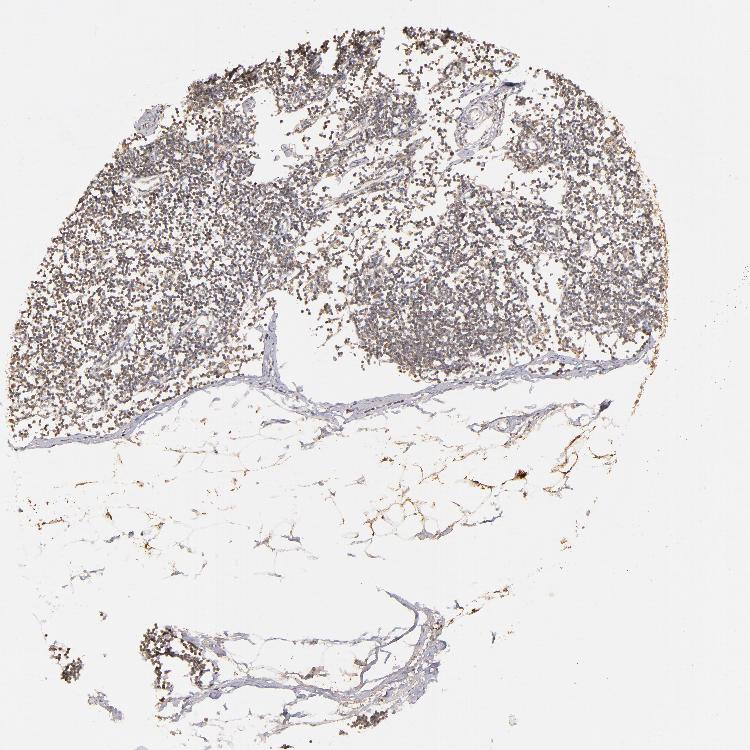

SOFT TISSUE 1 - Antibody stainingi

Antibody staining in the annotated cell types in the current human tissue is reported as not detected, low, medium, or high, based on conventional immunohistochemistry profiling in selected tissues. This score is based on the combination of the staining intensity and fraction of stained cells.

Each image is clickable and will lead to virtual microscopy that enables deeper exploration of all samples and also displays staining intensity scores, fraction scores and subcellular localization as well as patient and tissue information for each sample.

Antibody HPA002898

Fibroblasts Not detected

SOFT TISSUE 2 - Antibody stainingi